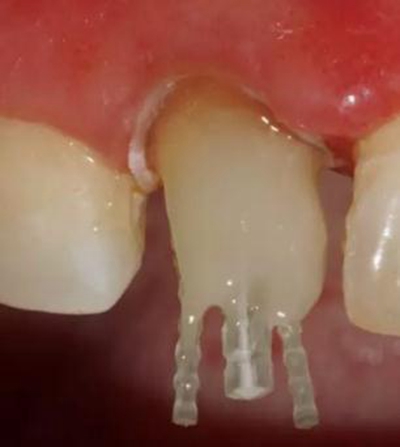

在操作的過(guò)程中要注意無(wú)菌操作,保證纖維樁的無(wú)菌狀態(tài)。推薦將樹(shù)脂核堆好之后再截?cái)嗬w維樁,而不是截?cái)嗪笤僬辰印H缦聢D:

10、排齦精修